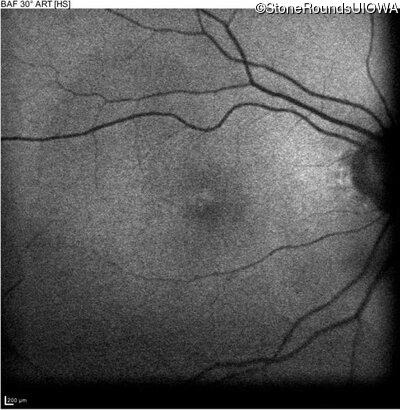

The clinical features favoring the diagnosis of RP1L1-associated occult macular dystrophy include: reduced acuity with a near-normal ophthalmoscopic appearance, a history of normal acuity in childhood; and, a "moth-eaten" appearance of the macular ellipsoid zone on OCT.

Age at visit: 70 years